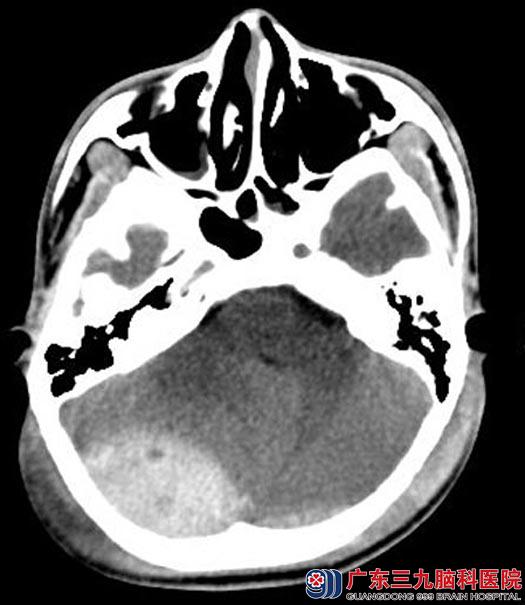

醒来后,阳阳想着起来帮忙干点家务活,由于还是睡眼惺忪的状态,阳阳没有留意脚下,一脚踩空,从三楼失足坠落。当即诉头痛,家属急送当地医院就诊,行头颅CT检查:双侧枕部少量硬膜外血肿,立即转入广东三九脑科医院综合神经外科。

手术前